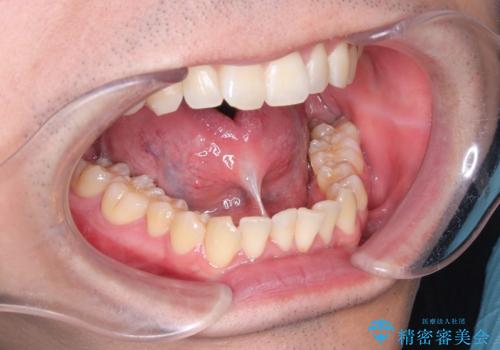

[舌小帯の形成術] 舌の動きが悪い 滑舌を改善したい!

滑舌の改善 舌小帯の形成術

[ 舌小帯の形成術 ] ラ行の発音を改善したい